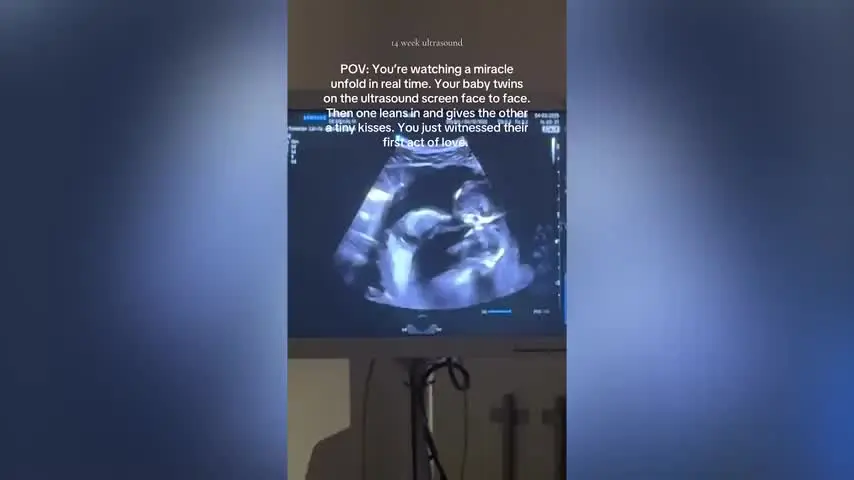

What appeared on the screen stopped time.

Doctors stared in silence… then awe.

This wasn’t a complication — it was a rare, breathtaking miracle.